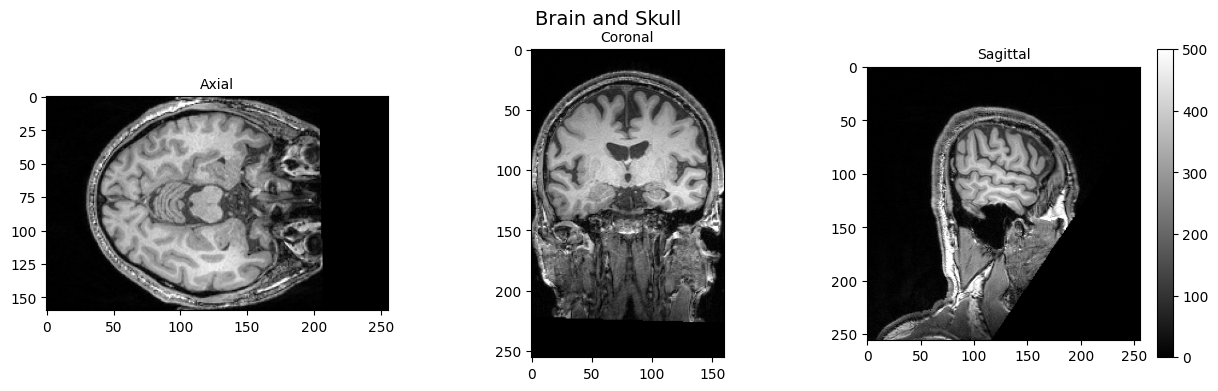

2025-12-22 09:10:26 | INFO | nipype.workflow | [Node] Setting-up "_tpms_std2t1w0" in "/home/jovyan/Git_repositories/neurodeskedu/books/examples/workflows/MRIQC_workdir/mriqc_wf/anatMRIQC/SpatialNormalization/434ab9539ec8d6d5b6ba6fe4782a83f00d15c331/tpms_std2t1w/mapflow/_tpms_std2t1w0".

2025-12-22 09:10:26 | INFO | nipype.workflow | [Node] Executing "_tpms_std2t1w1" <niworkflows.interfaces.fixes.FixHeaderApplyTransforms>

2025-12-22 09:10:26 | INFO | nipype.workflow | [Node] Executing "_tpms_std2t1w0" <niworkflows.interfaces.fixes.FixHeaderApplyTransforms>

2025-12-22 09:10:26 | INFO | nipype.workflow | [Node] Executing "drift" <mriqc.interfaces.diffusion.CorrectSignalDrift>